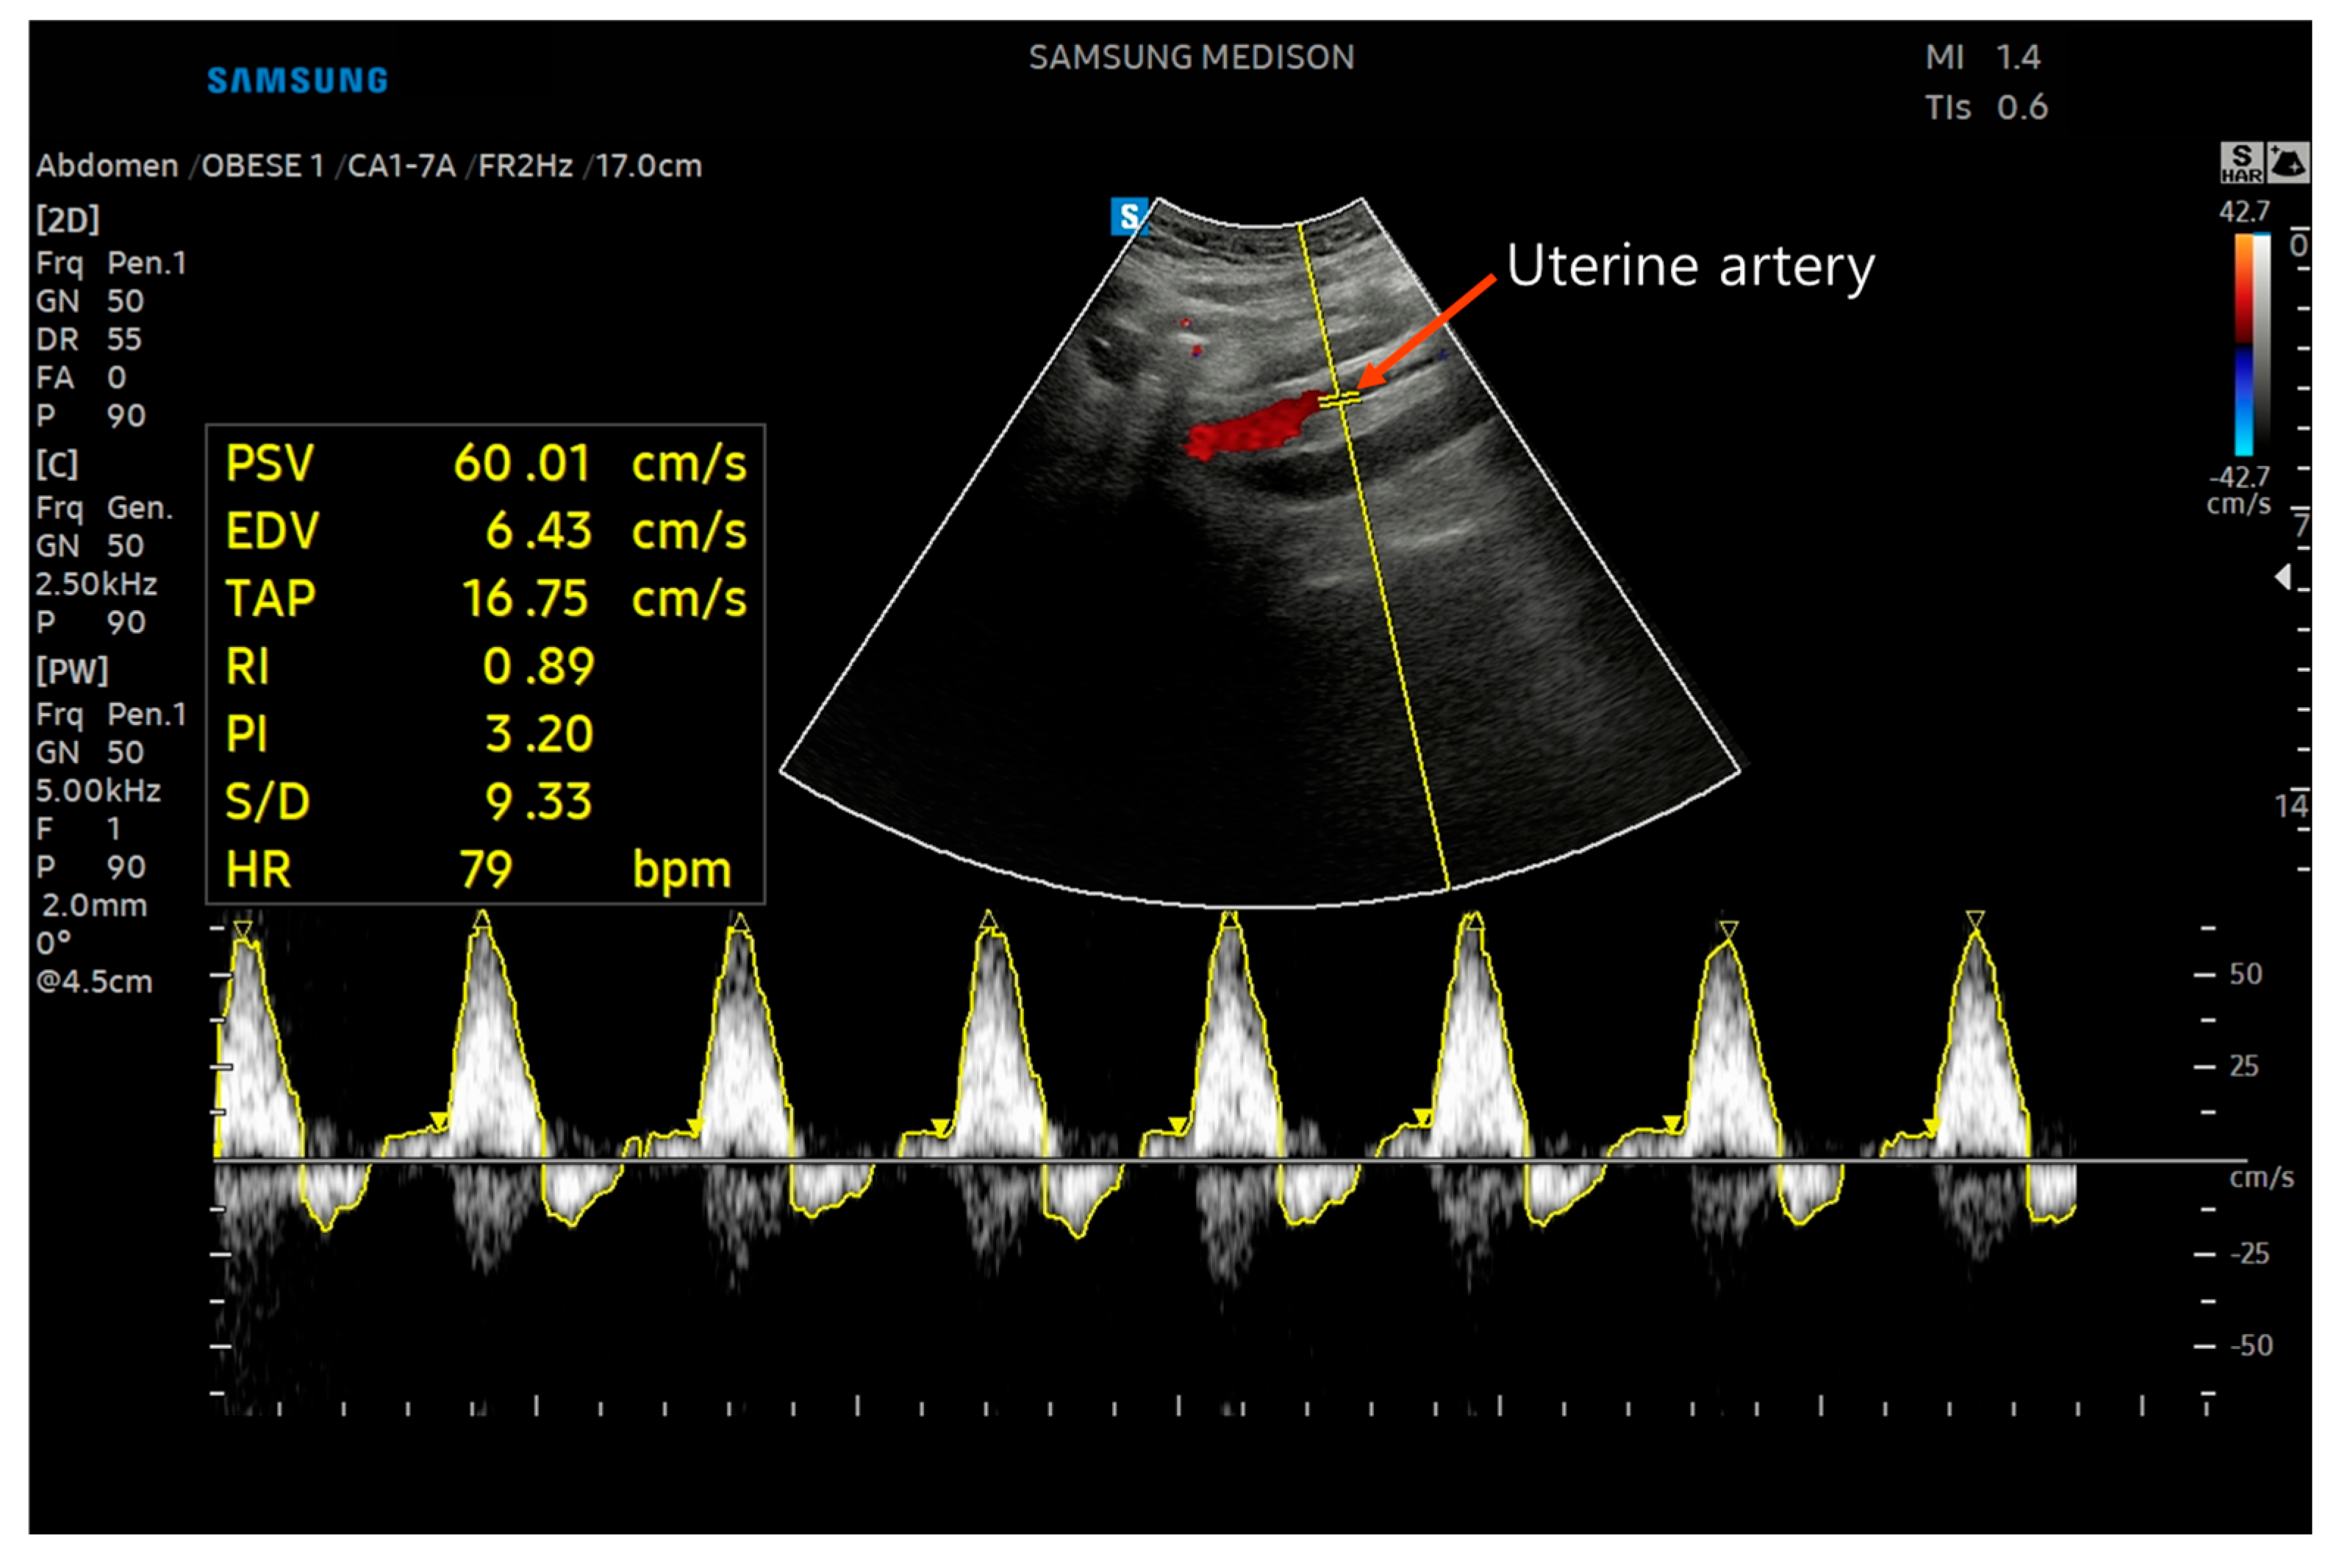

Uterine Artery Hemodynamic Indices

3.4. Uterine Artery Hemodynamic Indices

| UA_L | ||||||||||||

| PI | 3.66 (0.72) | 3.47 (0.72) | 3.72 (0.89) | 3.30 (0.92) | 3.14 (0.85) | 3.44 (0.84) | 0.07 (1.15) | −0.17 (1.17) | −0.51 (1.11) | −0.02 (1.11) | 0.24 [−0.29, 0.76] | −0.49 [−1.06, 0.08] |

| RI | 0.98 (0.04) | 0.96 (0.04) | 0.98 (0.08) | 0.93 (0.08) | 0.95 (0.08) | 0.95 (0.08) | −0.01 (0.09) | −0.03 (0.09) | −0.04 (0.09) | −0.01 (0.09) | 0.02 [−0.02, 0.06] | −0.03 [−0.09, 0.03] |

| UA_R | ||||||||||||

| PI | 3.71 (0.72) | 3.16 (0.72) | 3.50 (0.93) | 3.04 (0.96) | 3.01 (0.76) | 3.44 (0.76) | −0.21 (1.18) | −0.12 (1.20) | −0.69 (1.05) | 0.28 (1.05) | −0.09 [−0.69, 0.51] | −0.97 [−1.54, −0.39] |

| RI | 0.98 (0.04) | 0.94 (0.08) | 0.95 (0.08) | 0.91 (0.08) | 0.93 (0.08) | 0.96 (0.08) | −0.03 (0.09) | −0.03 (0.11) | −0.05 (0.09) | 0.02 (0.11) | −0.002 [−0.05, 0.05] | −0.07 [−0.11, −0.02] |